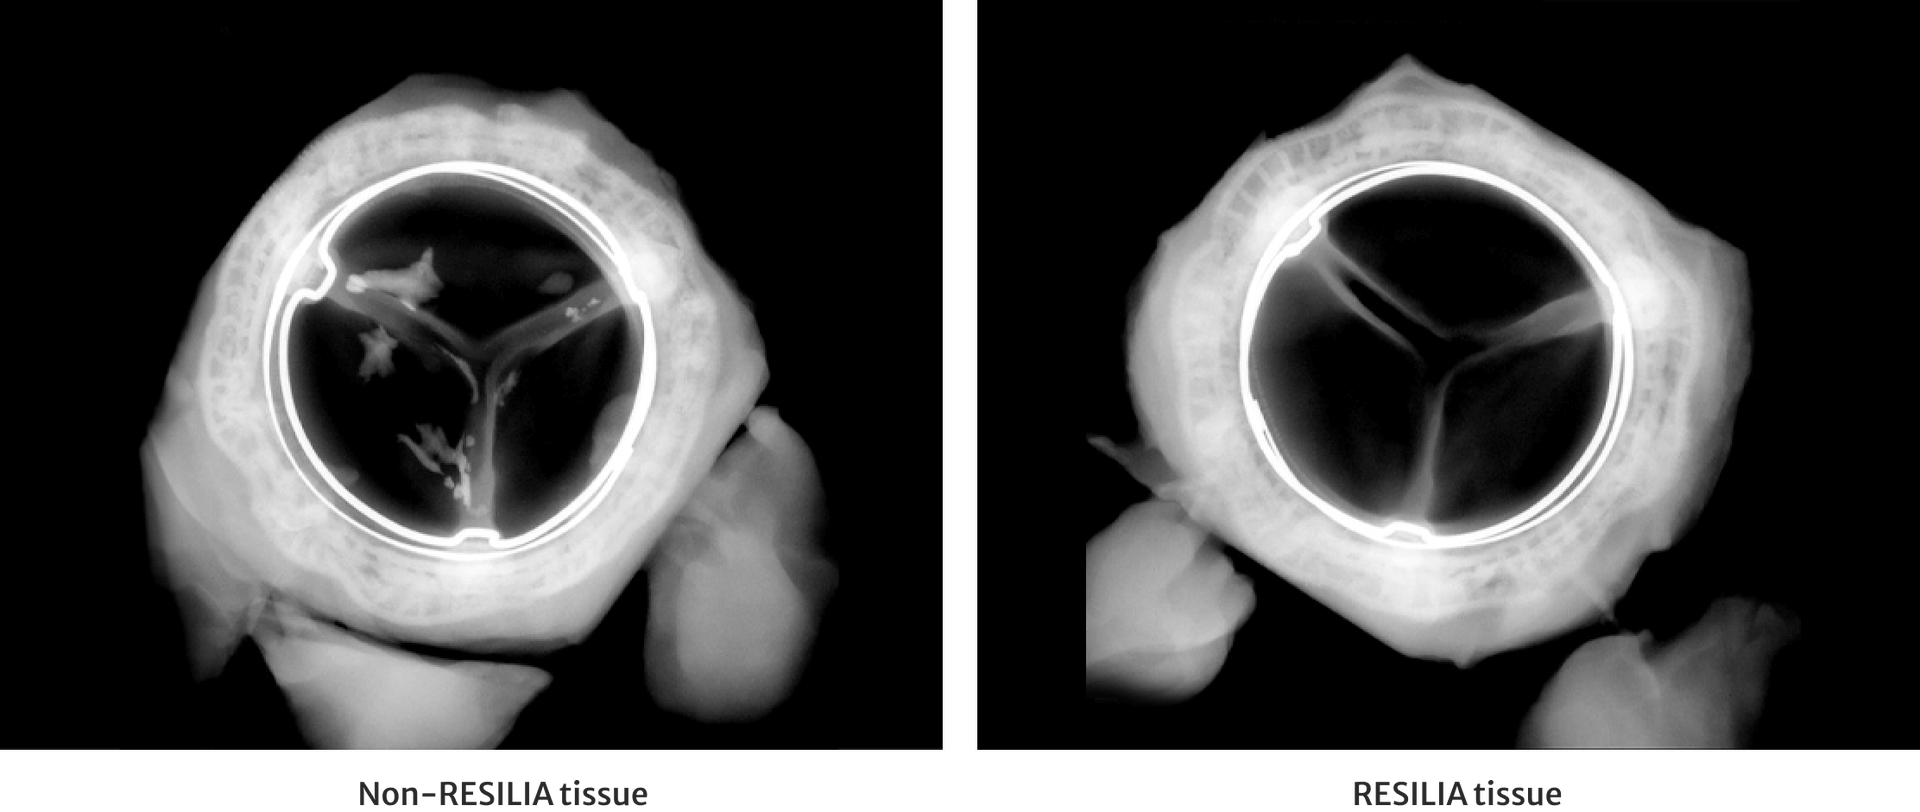

RESILIA tissue has demonstrated significantly less calcium build-up.3 Here you can see how RESILIA tissue (left) has less build-up of calcium on the valve leaflets than a non-RESILIA tissue valve (right).3